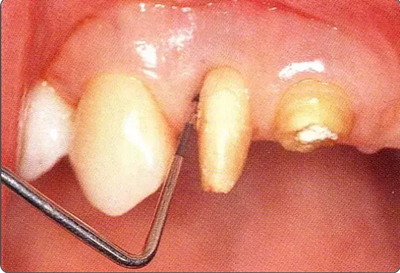

深牙周袋的治療

圖10-2  x片顯示的遠中部有垂直性骨缺損。